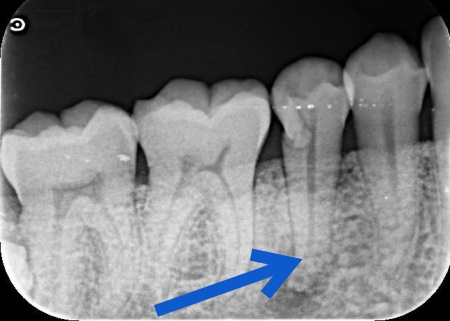

原因を調べるためにレントゲン検査を行ったところ、歯の根の先に炎症が起きている様子が確認できました。

さらに詳しく調べた結果、歯根の壁に穴があくパーフォレーションが起きており、その穴から細菌が入り込んで歯根の周囲に感染と炎症が広がっていると考えられます。